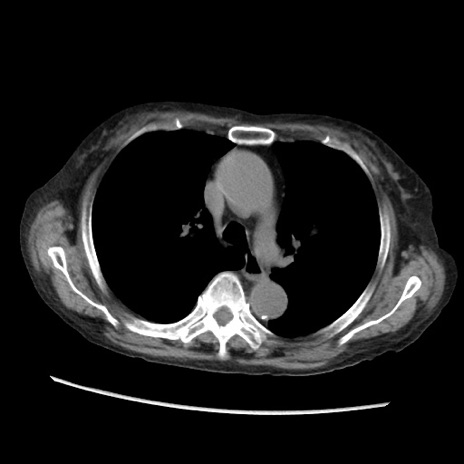

冠状断像